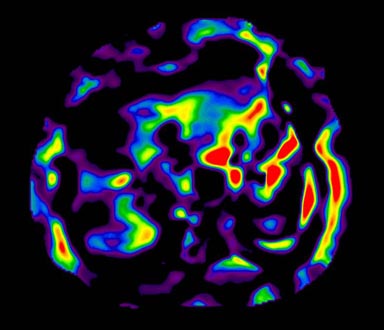

MR-Touch acquisition generates the following image types: magnitude, phase maps, wave maps, and an attenuation map. Six relative stiffness images are reconstructed for each slice location. The relative stiffness images are reconstructed in color and grey scale, and in masked and un-masked versions. Mask portion is depicted as a checkerboard pattern on the image. It is created to identify regions that should not be included in ROI measurements.

Figure 5. Color Elastogram, no mask, scale 0-8K

Figure 7. Color Elastogram, no mask, scale 0-20K